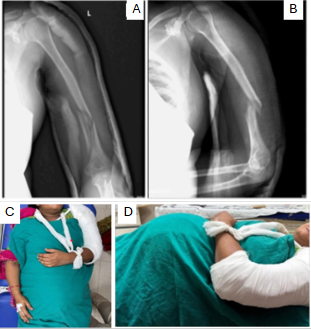

A 30-year-old primigravida at 38 weeks +4 days of gestation presented to the emergency department after a road traffic accident involving a four-wheeler collision. She reported pain and deformity in the left upper limb. The patient had no prior medical comorbidities, and her pregnancy had progressed uneventfully following spontaneous conception. She had adhered to routine antenatal care, including regular intake of iron and calcium supplements, two doses of tetanus vaccination, and standard antenatal screening. She was blood group O-positive and tested negative for Group B Streptococcus. Her menstrual history was unremarkable, with regular cycles occurring every 28–30 days, lasting 3–4 days with average flow. On presentation, the patient was alert, oriented, and hemodynamically stable (blood pressure 100/70 mmHg, heart rate [HR] 98 bpm, RR 18/min, and SpO2 99% on room air via left upper limb). She was afebrile, with no pallor or pedal edema. There was no history of loss of consciousness, ear, nose, throat bleeding, vomiting, or seizures. Local examination of the left upper limb revealed tenderness, swelling, and deformity without any open wounds. Motor and sensory functions were preserved, and radial and ulnar pulses were palpable. Abdominal examination revealed a uterine fundal height consistent with 36 weeks, a longitudinal lie, cephalic presentation, and a tense, rigid uterus. Irregular uterine contractions (2–3/10 min) were noted, along with reduced fetal movements. Cardiotocography (CTG) showed a baseline fetal HR of 175 bpm, with recurrent late decelerations and reduced beat-to-beat variability (<5 bpm). Doppler studies revealed increased umbilical artery resistance (pulsatility index [PI]: 1.48; S/D ratio: 4.2) and a decreased middle cerebral artery PI (PI: 0.82), resulting in a cerebroplacental ratio of 0.55 – indicative of a brain-sparing effect and consistent with intrauterine hypoxia. A non-stress ultrasound showed normal amniotic fluid volume and a singleton fetus in cephalic presentation with no placental or uterine abnormalities. The cervix was 2 cm dilated but closed. Routine laboratory investigations, including complete blood count, coagulation profile, and crossmatch, were within normal limits. Given the gestational age and maternal stability, a trauma protocol was activated involving obstetrics, orthopedics, anesthesiology, and neonatology teams. Plain radiographs of the right arm (with pelvic shielding) revealed a wedge-type diaphyseal fracture of the humerus (AO type 12B2). Closed reduction under traction was performed, and immobilization was achieved with an upper arm (U) slab(Figure 1). Given signs of fetal compromise – possibly due to placental abruption – the multidisciplinary team recommended conservative orthopedic management until delivery.

Figure 1: Pre-operative radiographs of left arm anteroposterior (a) and lateral (b) view showing a displaced distal 1/3rd shaft humerus fracture (AO type 12B2) with overriding fragments, and clinical images (c and d) showing limb immobilization in a U-slab in a third-trimester pregnant patient.